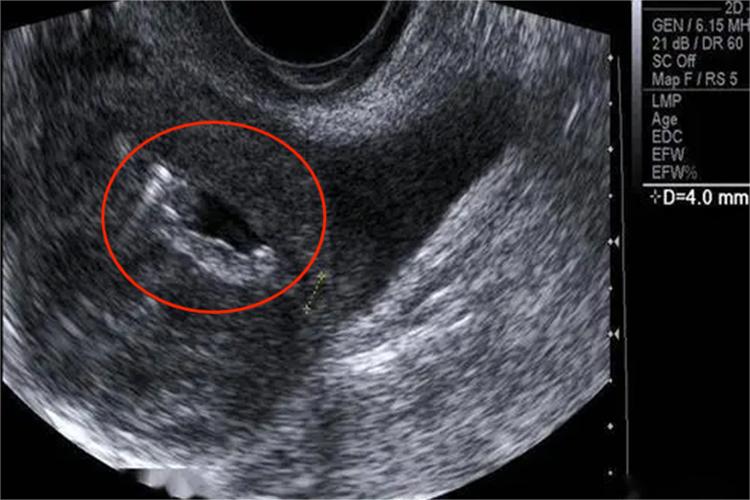

超声表现:B超检查时较小穿孔不易显示,仅在直肠子宫陷凹探及积液改变;穿孔较大时,宫体可略增大,子宫壁和(或)内膜回声连续性中断,呈低回声,并有外界气体进入形成的线状强回声穿透;出血量多时,可波及腹腔,表现为移动性无回声区,多出现在下腹两侧。